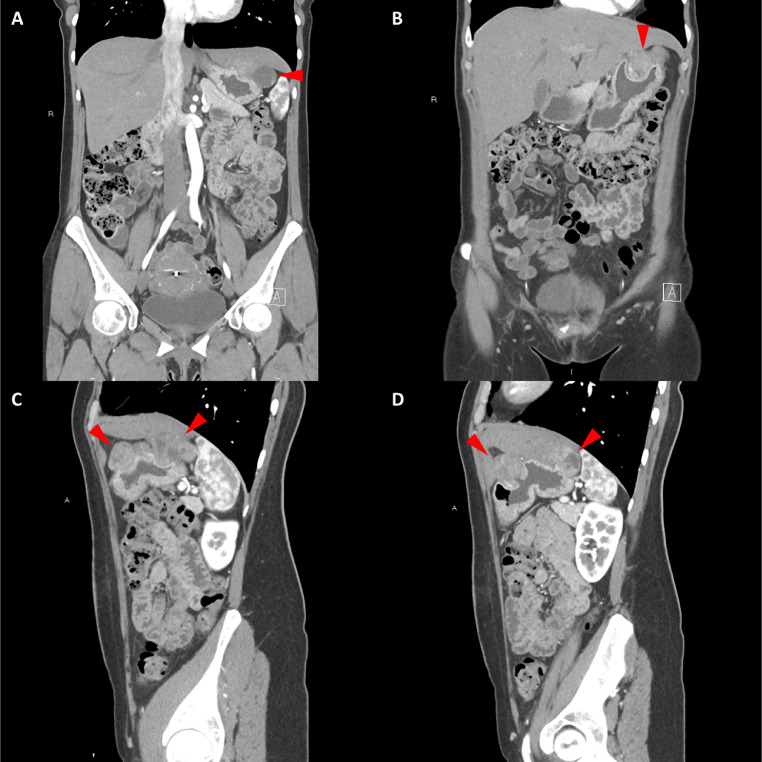

胸部、腹部和骨盆的對比增強動脈和靜脈期 CT 顯示多個圓形、主要是血管豐富的異質腫塊,具有囊性和實性成分,起源于胃底和胃體(圖 2-4)。 病變部分呈外生結構,被認為位于粘膜下層。 在頸部多發(fā)同步性副神經節(jié)瘤的情況下,賊初的鑒別診斷包括多發(fā)性副神經節(jié)瘤、多發(fā)性 GIST 以及轉移性疾病。

圖 2:多發(fā)胃腸道間質瘤的軸位 CT 圖像。 (A 和 B)軸位動脈相增強 CT 圖像和(C 和 D)軸位靜脈相增強 CT 圖像顯示多個圓形、不均勻、增強的腫塊,具有實性和囊性成分。 腫塊位于粘膜下,結構呈外生。

圖 3:多個胃腸道間質瘤的冠狀和矢狀圖像。 (A 和 B)冠狀動脈相對比增強 CT 圖像顯示胃賁門產生的外生性腫塊。 (C 和 D)矢狀動脈相位對比增強圖像顯示腫塊的異質性和外生結構。